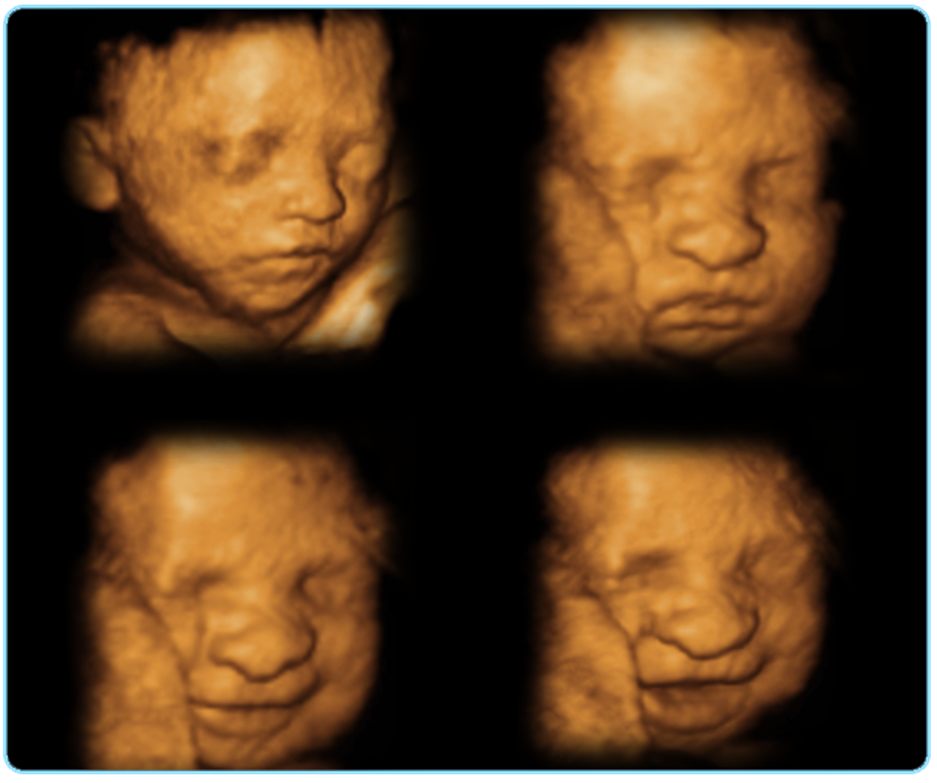

Una de las innovaciones más recientes y de mayor impacto en el campo del diagnóstico prenatal ha sido la incorporación de la Ecografía 3D . Esta nueva tecnología ha supuesto un cambio importante porque ahora obtenemos imágenes con volumen en lugar de imágenes planas. Además, se pueden visualizar los movimientos del feto en tiempo real que es la llamada Ecografia 4D . Uno de los puntos más importantes relacionado con la ecografía 4D es que la imagen en tiempo real que se obtiene permite a los padres crear un vínculo afectivo madre-hijo muy fuerte.

La semana ideal para realizarte este tipo de ecografía es a partir de la semana 24 y hasta la 30, más tarde puede ser que no se vea con tanta claridad, debido a que el feto es demasiado grande y existe poco liquido amniótico

Tenemos la última tecnología en ecografías 3D y 4D . Excelentes instalaciones a su servicio.